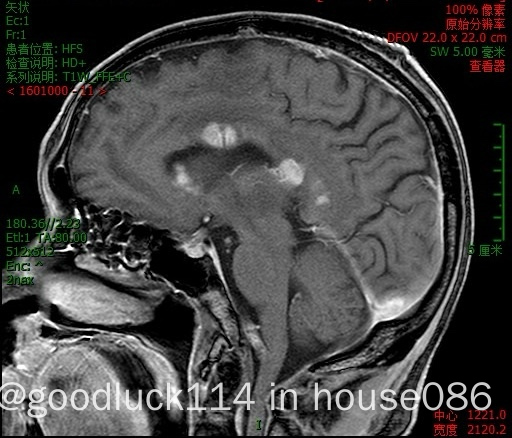

高龄取不了病理,医院做不了pet-ct,做了头颅ct和mri,发现颅内占位性病变,怀疑原发或转移,但胸部ct腹部ct和肿瘤标志物都没有明显异常,也没有除神经系统外其他系统的症状,mri增强结果不像是胶质瘤,高度怀疑是原发性中枢淋巴瘤。